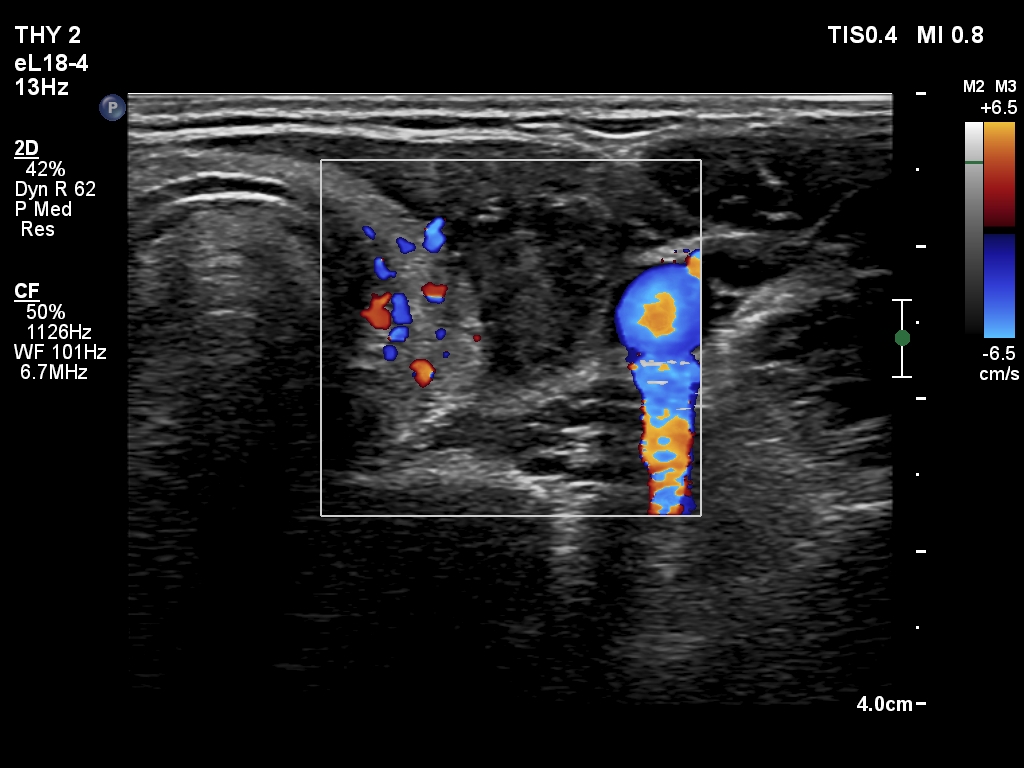

Ultrasonography. The thyroid was echonormal. There was a dominantly cystic nodule in the left lobe. The lesion had echonormal solid area.3.5 mL brown fluid was aspirated. The cyst has begun to refill during the aspiration of the cystic content. Cytology resulted in benign cystic lesion.

Ultrasonography. The pattern was the same as what we saw at the first examination except for an increase in nodule volume.

Ultrasonography. A minimally hypoechoic-echonormal mass has appeared within the nodule. By compression, we could detect flow of the mass.

Ultrasonography. A minimally hypoechoic-echonormal mass has appeared within the nodule. By compression, we could detect flow of the mass.